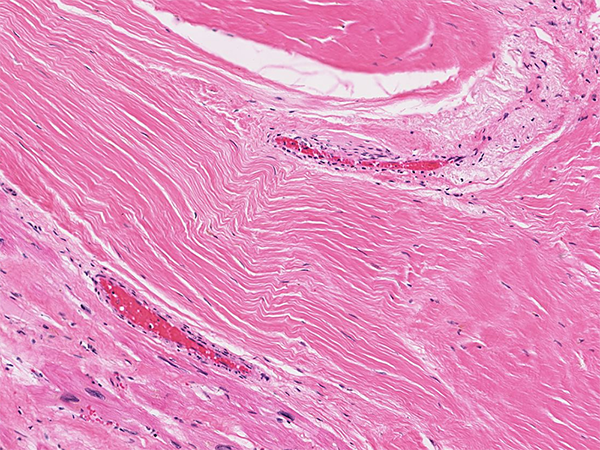

Constitutively Active Repair:

Sometimes the signals that cause repair to progress to mature scar become stuck in the "on" position

Examples of this include excessive granulation tissue ("proud flesh"), keloid scars, and idiopathic pulmonary fibrosis

Do the following image represent up- or downregulated repair?